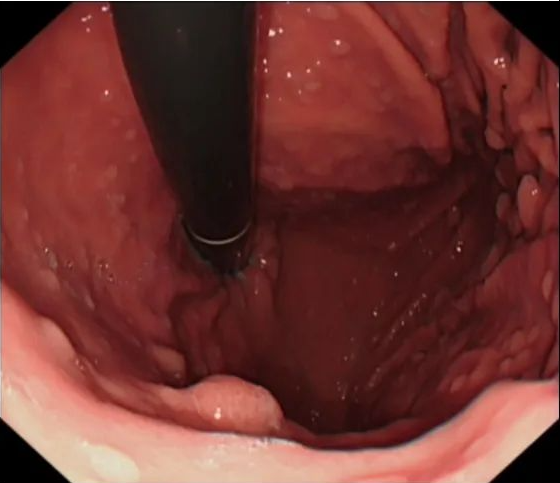

检查结果证实了大家的推测,患者胃镜提示:置底、体见弥漫性大小直径约0.5-2.0cm广基隆起,表面粗糙,边界清楚。胃窦见一大小约5x13cm隆起,呈分叶状.表面粘膜粗糙,边界尚清楚。肠镜见全结肠弥漫性大小约0.5-1.0cm 广基隆起。胃窦较大病变予取材送检,病检回报示:错构瘤性息肉。患者胃窦巨大病变,若不及时切除癌变风险极大,但患者年纪较轻,如果进行传统外科胃大部分切除术对患者后续生活质量影响较大。经讨论后,为患者进行胃镜下胃窦病变粘膜下剥离术为最佳手术方式,但是因患者病变巨大,手术难度大,剥离过程中出血及穿孔风险极大,这也为手术增加了不少难度。与此同时患者强烈要求就在本院进行手术治疗。

本着信任和解决难题的初衷,经过全科病历讨论后为患者制定了详细的手术方案及术前准备,历时六个小时,终于成功为患者完成了内镜下胃窦巨大肿物ESD 术,瘤体完整剥离,创面无残留,术中出血約50m1,离体标本大小5. 0X13CM。内镜诊断。术后病检符合P-J息肉诊断。